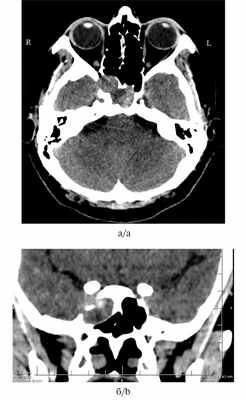

Консультация нейроофтальмолога: смыкание век полное, острота зрения OD=0,9—1,0, OS=0,9—1,0. Поля зрения не изменены, корнеальные рефлексы справа и слева в норме, реакция на свет удовлетворительная, конвергенция в норме, движение глазных яблок в полном объеме, справа и слева диск зрительного нерва розовый, границы четкие, артерии не изменены, вены умеренно полнокровны. Признаки застойных зрительных дисков отсутствуют, нейроофтальмологической симптоматики нет. На компьютерной томограмме околоносовых пазух определяется новообразование клиновидной пазухи справа с деструкцией костей средней черепной ямки (рис. 1а, 1б).

Рис. 1. Пациентка Б. Компьютерная томография носа и околоносовых пазух.

а — аксиальная проекция; б — фронтальная проекция. Десмопластическая фиброма клиновидной пазухи справа с деструкцией костей средней черепной ямки.